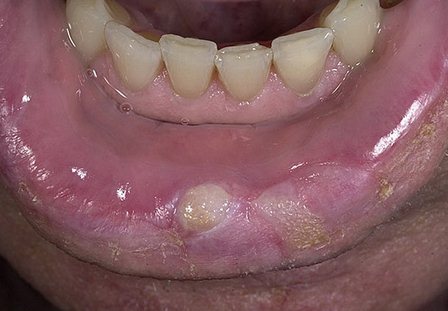

В первую очередь на появление «вражеских» клеток реагируют подбородочные лимфоузлы, воспаляясь и становясь подвижными. Их можно легко заметить, ощупывая нижнюю челюсть. Далее на поверхности нижней губы возникает припухлость, которая слегка зудит и имеет плотную консистенцию. Даже если у вас появятся эти симптомы рака губы, скорее всего вы не обратите на это внимание и примите за простуду. В это время в центре припухлости уже образовалась язвочка с валикообразным краем, имеющая нечеткие границы. В центре этой язвочки – корочка, которая безболезненна сама по себе, но при удалении может вызывать боль. Если убрать эту корочку, то можно увидеть кровоточащее основание, образованное бугорками.

Симптомы рака губы можно не заметить на начальной стадии, но в дальнейшем они дадут о себе знать. Опухоль может развиваться медленно, в ряде случаев этот процесс может протекать в течение нескольких лет. Вскоре вокруг нее появляется инфильтрат – скопление раковых клеток с примесью крови. Также можно заметить, что лимфоузлы значительно уплотнились, а губа стала менее подвижной и будто срослась с челюстью и в подобном состоянии человеку попросту становится трудно есть. Затем появляется небольшая деформация губы, возникает неконтролируемое истечение слюны. Постепенно ткань опухоли распадается, а на фоне нарушенного питания развивается кахексия (истощение организма). Метастазы опухоли могут распространяться на лимфатические узлы, которые впоследствии начинают превращаться в инфильтраты. Метастазы также могут поразить кости, тем самым разрушая челюсть.